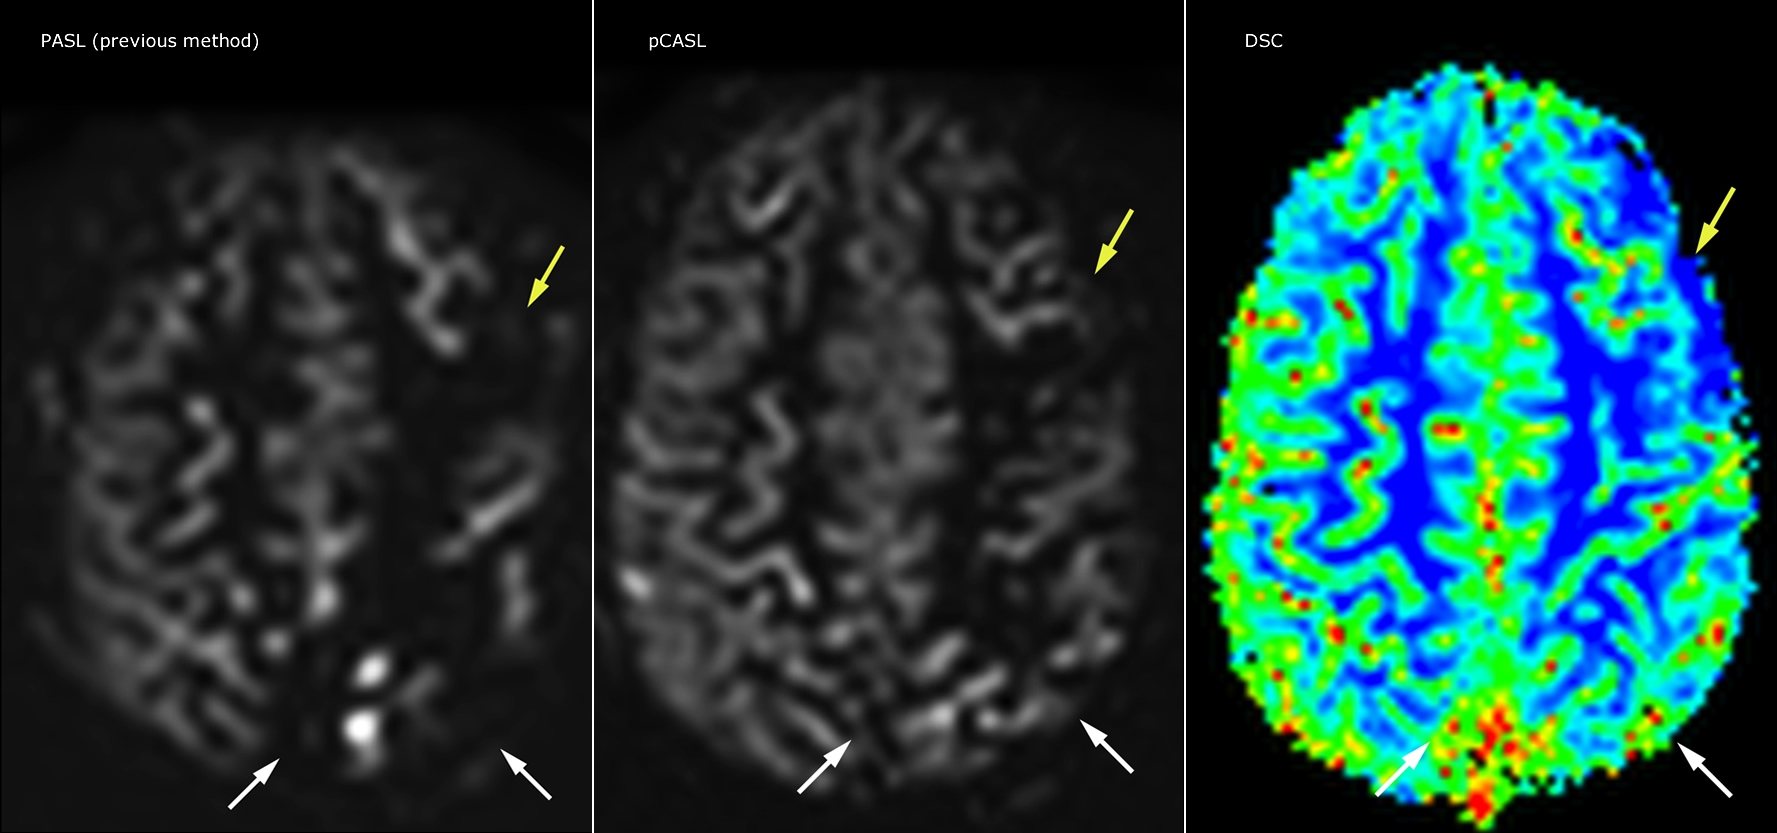

pCASL helps assess brain perfusion without contrast

Pseudo-continuous arterial spin labeling (pCASL) was developed for brain perfusion imaging without contrast agent. “This is very desirable in pediatric patients where the general trend is to limit the administration of contrast,” says Dr. Miller.

Dr. Miller uses pCASL for all patients who present with chronic and acute cerebrovascular abnormalities such as acute stroke, as well as patients who present with signs of acute inflammation in the brain, and occasionally in patients with tumors, to assess the perfusion status of their tumor.

“In combination with diffusion weighted imaging, it can help give a more extended assessment of the degree of perfusion abnormality in a patient who is suffering acute ischemia. We have a number of patients who have chronic arterial insufficiency due to prior arterial abnormalities or acquired arterial abnormalities such as sickle cell disease or neurofibromatosis. Sometimes the child’s first manifestation of disease progression is a reduction in brain perfusion before stroke symptoms manifest clinically or in diffusion weighted imaging. We use pCASL to help delineate the perfusion abnormality.”

Growing confidence in specific applications

“We built up confidence in pCASL by comparing it to contrast-based perfusion imaging. Once we had confidence that it was representing what the contrast perfusions were representing, we increased our diagnostic confidence by serial imaging in either the acute stage or the long term stages in a number of patients with arterial abnormalities.

To other new users I would recommend to also start to interpret the pCASL images in comparison with other standard imaging – T2 and FLAIR and DWI – until the user gains confidence in interpreting these images by themselves.”

“A powerful use of pCASL is in patients with chronic cerebrovascular stenosis, where clinicians desire information on how compensatory mechanisms of the brain are performing to enable perfusion to the brain. Often clinicians take into account how the compensatory mechanisms appear to help to provide adequate perfusion to the patient’s brain, and they may intervene surgically or make some other management decision.”

“Another special application is the assessment of cerebrovascular reactivity with a Diamox perfusion exam, where we subtract two sets of pCASL images.”

Efficiencies gained with pCASL

“pCASL has now become more of a first-line scan for assessing perfusion for us, as opposed to DSC-based perfusion imaging with contrast agent. And in patients who were not planned to have contrast, we can perform pCASL for perfusion imaging without need to stop the exam, pull the patient out, and put in an IV. It also negates the postprocessing that’s necessary for dynamic susceptibility contrasts. And it allows us to repeat perfusion imaging in the same patient at the same imaging time, which is helpful in terms of patient motion, or in a situation where a scan needs to be done before pharmacological perfusion imaging.”

Goetti R, O'Gorman R, Khan N, Kellenberger CJ, Scheer I.  Arterial spin labelling MRI for assessment of cerebral perfusion in children with moyamoya disease: comparison with dynamic susceptibility contrast MRI.  Neuroradiology. 2013 May; 55(5):639-47, Epub  2013 Feb https://www.ncbi.nlm.nih.gov/pubmed/23404242